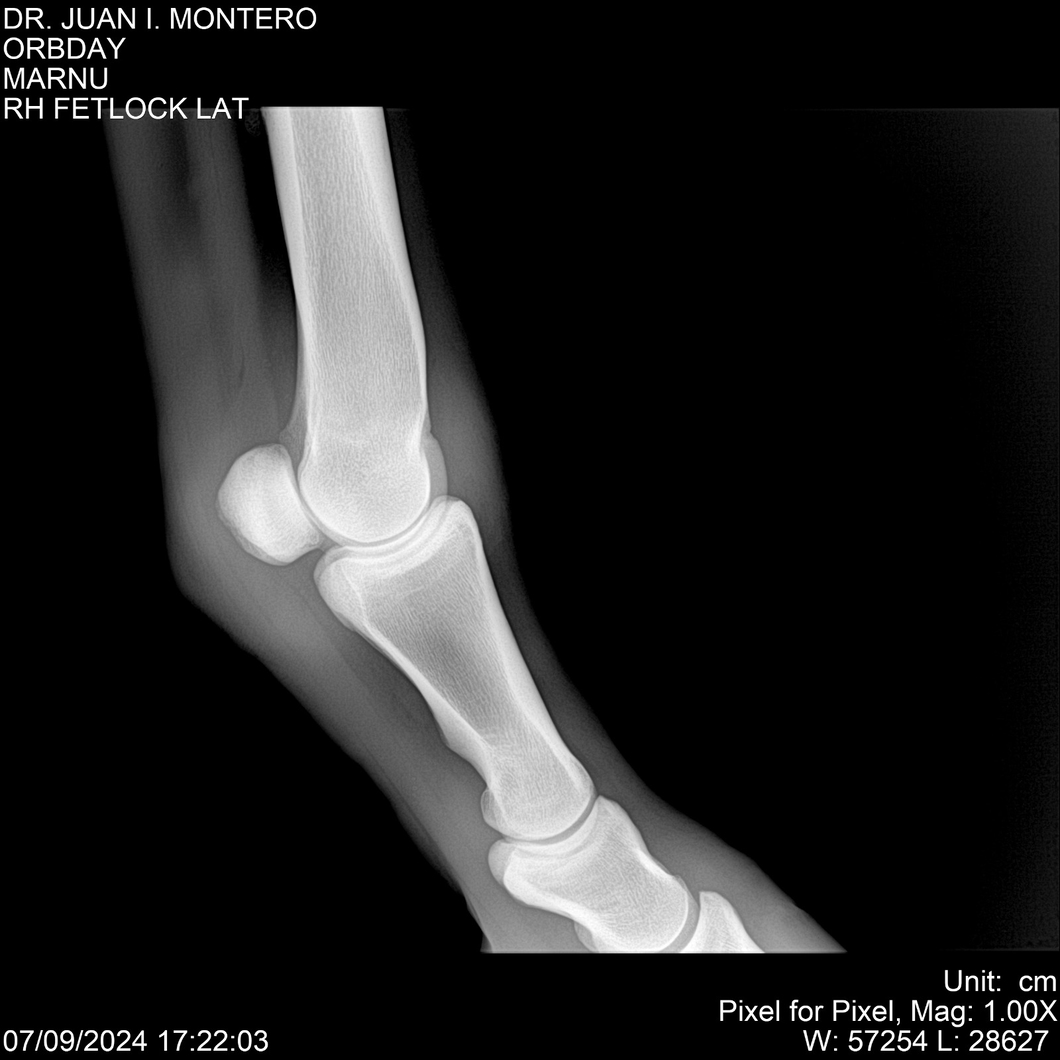

• Empresa: Abelenda N. R., Walter Hugo